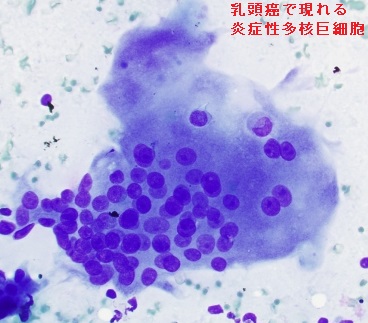

[血液検査で炎症反応(WBC, CRP)も陽性で、炎症部の穿刺細胞診でも癌細胞検出されず、亜急性甲状腺炎と勘違いします。ステロイド治療で炎症治まれば、低エコー領域は縮小しますが、甲状腺乳頭癌本体は消えないため、再度の穿刺細胞診で診断されます。手術摘出後の病理標本では、甲状腺乳頭癌周囲のリンパ球浸潤が確認されます。]

で痛みが生じることがあります。亜急性甲状腺炎と高をくくっていても、甲状腺超音波(エコー)検査で甲状腺乳頭癌だった症例報告があります。

亜急性甲状腺炎に甲状腺乳頭癌が合併

ステロイド治療の後、甲状腺全体の腫れが引くと、甲状腺乳頭癌の低エコー域も縮小するので、亜急性甲状腺炎の炎症と勘違いする可能性があります。例え縮小しても、消えなければ、しかも石灰化を伴っていれば甲状腺乳頭癌を疑うべきです。亜急性甲状腺炎が沈静化しない内に穿刺細胞診すると、炎症所見が混ざって、病理医が甲状腺乳頭癌の診断を下し難い様です。